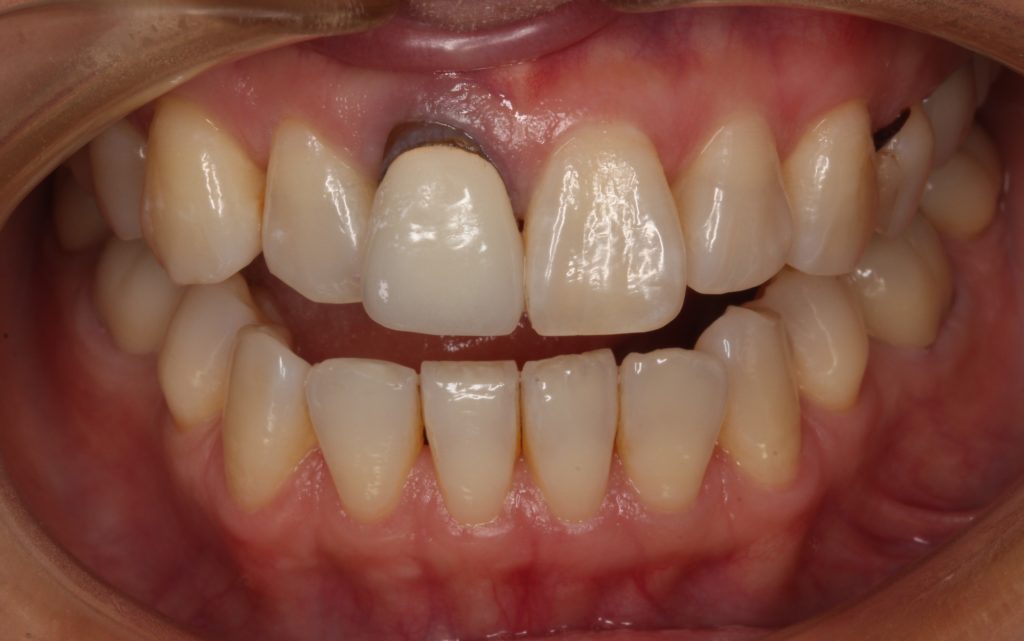

まずは被せ物をを削って外していきます。

被せ物を外した歯です。

歯が全体的に黒く変色しています。

根元は、被せ物を外すと良く分かりますが自身の歯の根元が出ていたのが分かります。

先端は銀色のメタルコアが見えています。